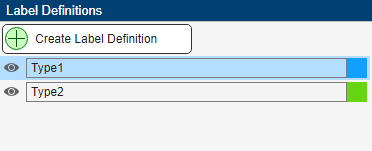

Create Label Definitions

In the Label Definitions pane, select Create Label Definition to create a label with the default label name. To change the name of the label, double-click on the label and type in a new name. The label name must be a valid MATLAB® variable name with no spaces. To change the default color associated with the label, double-click on the colored square in the label identifier and select a color from the Color dialog box. For this example, create two labels named Type1 and Type2.